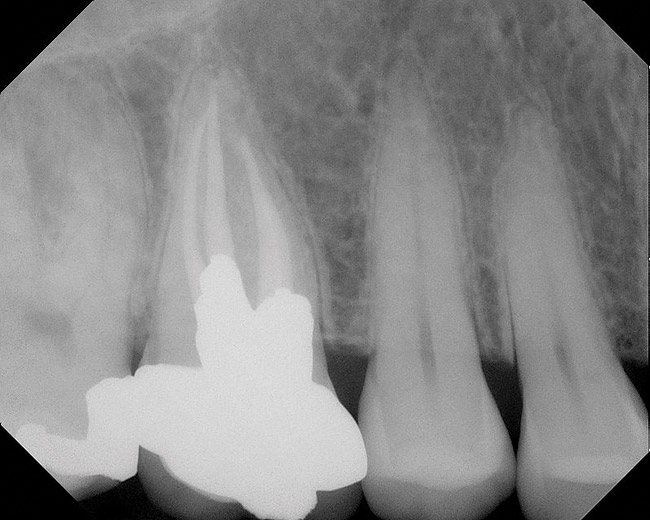

As mentioned, all risk factors associated with both root canal and implant therapy must be carefully considered. Comprehensive clinical and radiographic assessments are necessary to evaluate the patient's risk factors associated with his or her particular case (Figure 1, Figure 2 and Figure 3). The primary risk factors for implants can include smoking, bone quality, and systemic health. For endodontic therapy the primary risk factors are related to the anatomic root complexity, failed root canal treatment with significant technical defects manifested as iatrogenic events, less-than-optimal periodontal status of the tooth (due to a subsequent risk of vertical fracture), and a clinician's lack of experience with regard to the case's complexity. A strong correlation exists between failed root canal treatment and a lack of coronal seal after treatment. This is highly relevant in treatment planning. Often, endodontically treated teeth fail not because they were treated inappropriately and need extraction, but rather, because they have been left unsealed and assaulted by bacteria after the endodontic therapy, causing subsequent long-term clinical failure (Figure 4 and Figure 5).

While not elaborated on here, it is noteworthy that there are a number of additional treatments for resorption that have been suggested in the literature, including calcitonin,27 Emdogain,24,28 and Alendronate (third-generation bisphosphonate in treating EIRR)29 (Figure 6, Figure 7, Figure 8, Figure 9, Figure 10, Figure 11, Figure 12, Figure 13, Figure 14 and Figure 15).